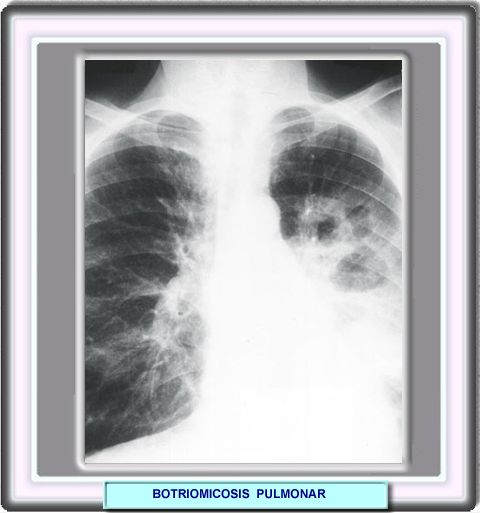

BOTRIOMICOSIS

En un 30% de los casos, la botriomicosis cutánea suele ir acompañada de infecciones viscerales. Los órganos más afectados son el hígado, los riñones, la próstata, los intestinos y la tráquea. Recientemente, se ha descrito la botriomicosis pulmonar En su mayoría los pacientes afectados son pacientes que presentan algun otro problema subyacente. Algunos de los factores que se cree están implicados son la inmunodeficiencia celular, la diabetes mellitus, el tratamiento crónico con corticosteroides y la fibrosis cística. El tratamiento antibiótico dependerá de la naturaleza y sensibilidad de los gérmenes que se detecten. |